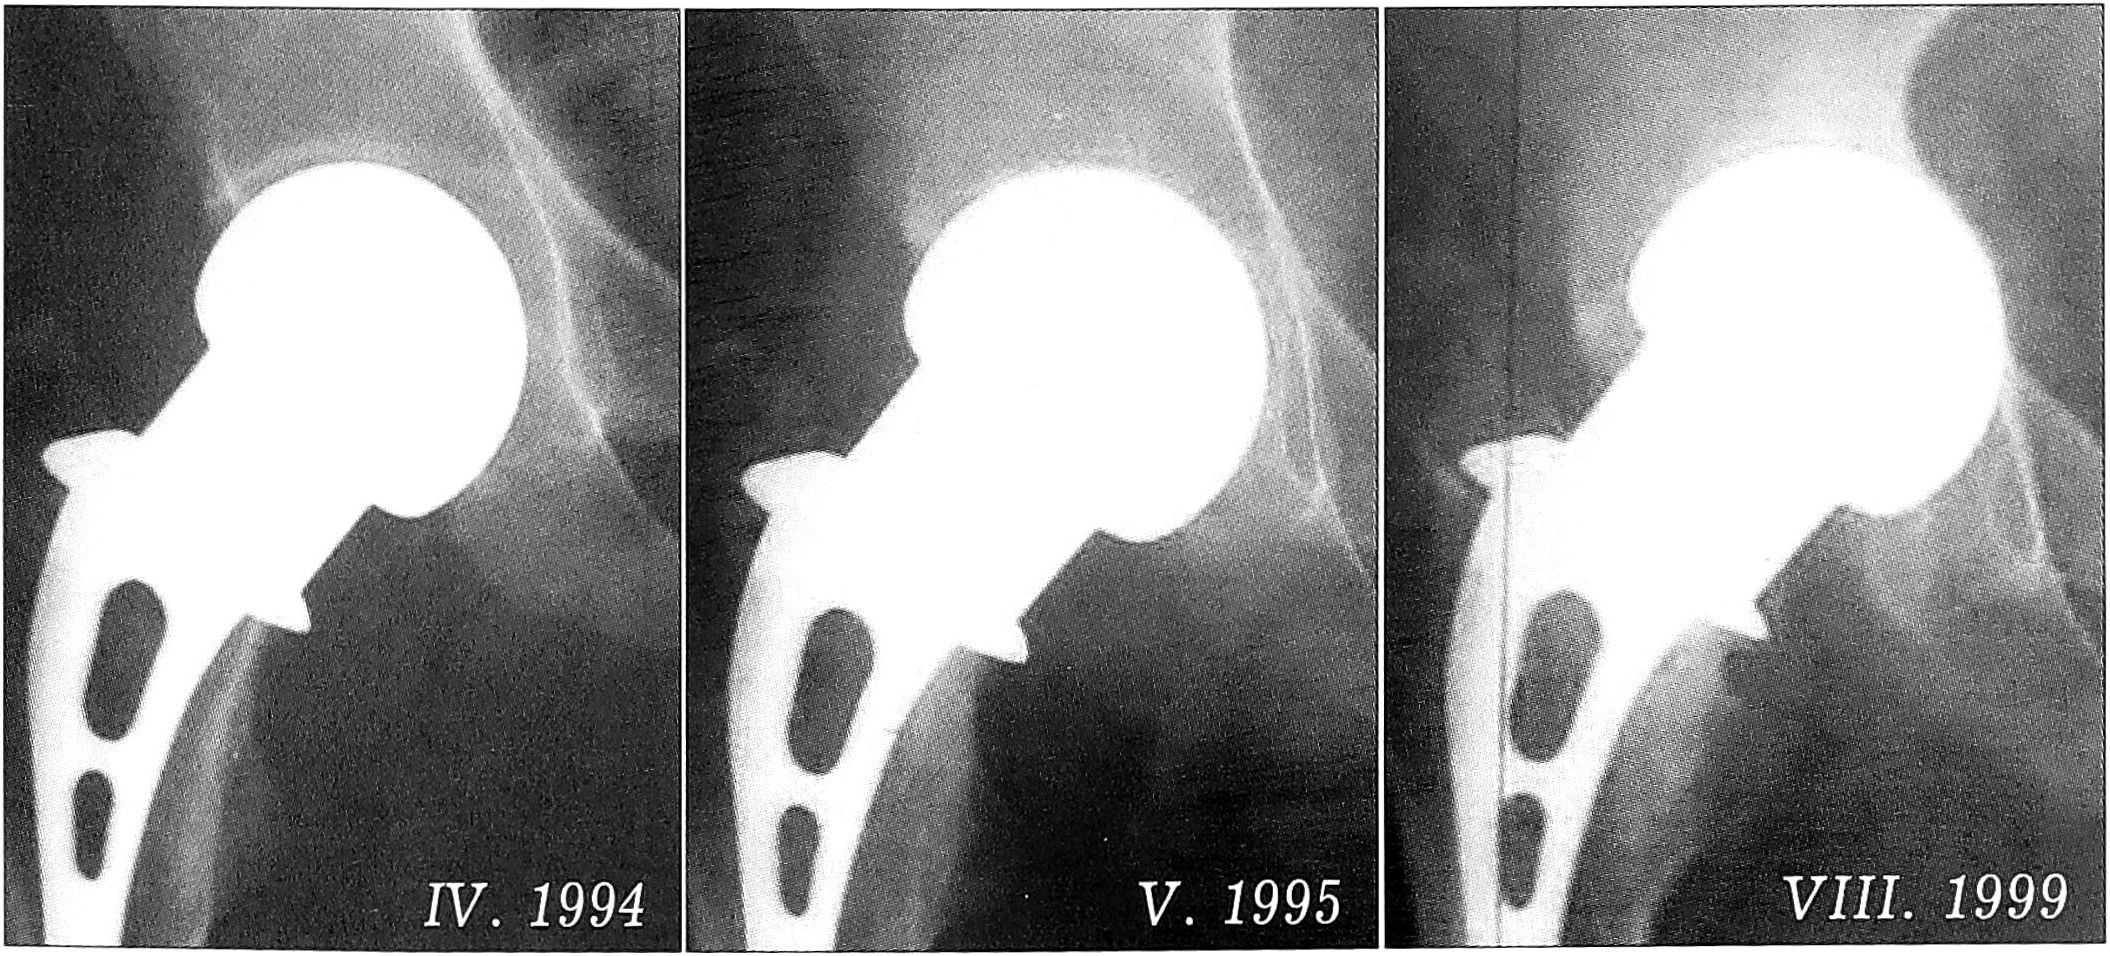

Использование монополярных эндопротезов имеет свои положительные стороны — низкая стоимость конструкции, простота, меньшая травматичность и продолжительность операции, однако при этом чаще отмечается расшатывание ножки протеза (при применении устаревших моделей) или протрузия его головки в вертлужную впадину (рис. 1).

Рис. 1. Развитие протрузии головки эндопротеза Мура—ЦИТО в вертлужную впадину в течение 5 лет.